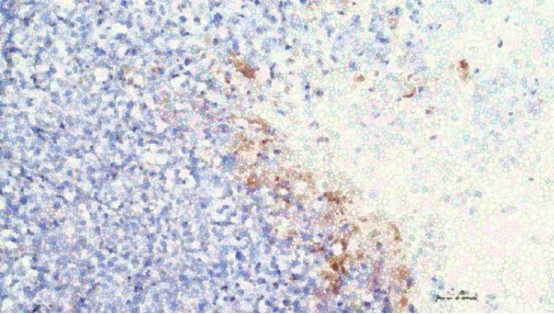

In Tiermodellversuchen zeigte sich bei Tumoren, bei denen das NRF2-Gen direkt ausgeschaltet wurde, ein signifikant verlangsamtes Wachstum. Studien haben gezeigt, dass die Bearbeitung von nur 20 bis 40 % der Zielgene in Tumorzellen die Wirksamkeit der Chemotherapie steigern kann. Die Forscher verwendeten Lipid-Nanopartikel als Transportmittel, und die Gensequenzierung bestätigte die hohe Spezifität dieser Methode. Seniorautor Dr. Eric Kermik merkte an: „Diese Forschung verändert unser Verständnis der Behandlung von arzneimittelresistenten Krebsarten. Mithilfe der Genomeditierungstechnologie können wir bestehende Medikamente wieder wirksam machen.“